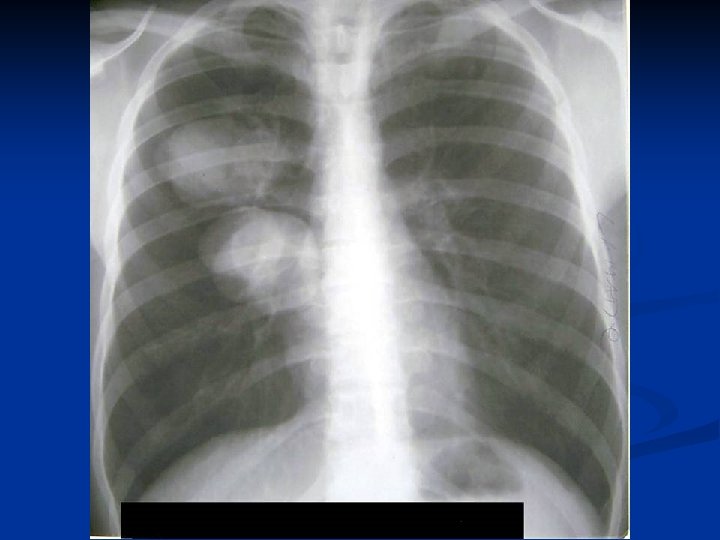

Caracteristici generale n n n Boala parazitara determinata de Taenia echinococcus granulosus. Descrisa inca de pe vremea lui Hipocrat si a lui Galen. Termenul de “chist hidatic” utilizat de Rudolphi in 1908. Localizarea pulmonara este a doua ca frecventa dupa cea hepatica. Boala cu distributie endemica in regiunea mediteraneana, Orientul Mijlociu, Australia, Noua Zeelanda, America de Sud.

Distributie in functie de faza evolutiva

Metode de diagnosticare